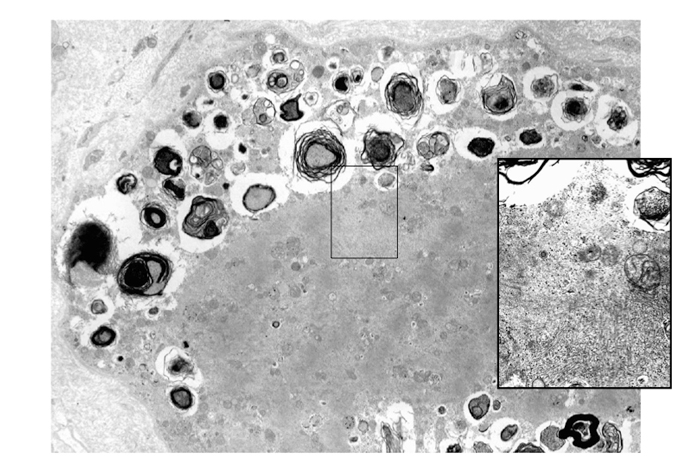

縁取り空胞を擁する線維ではしばしばTDP-43、p62、アミロイド陽性物質、ユビキチン陽性物質、そのほか多くの異常蛋白が検出できる。封入体は電子顕微鏡では横径約20 nm の管状または線維状の構造で、主に変性産物を中に含む空胞の近傍や一部の核内に見られる(Fig.52)。

Fig.52

縁取り空胞はmyelin figure とよばれる脂質を含む筋変性産物といわれる構造をなかにようする空胞で、その近傍には直径約20nmの線維性封入体が多くの場合存在する。